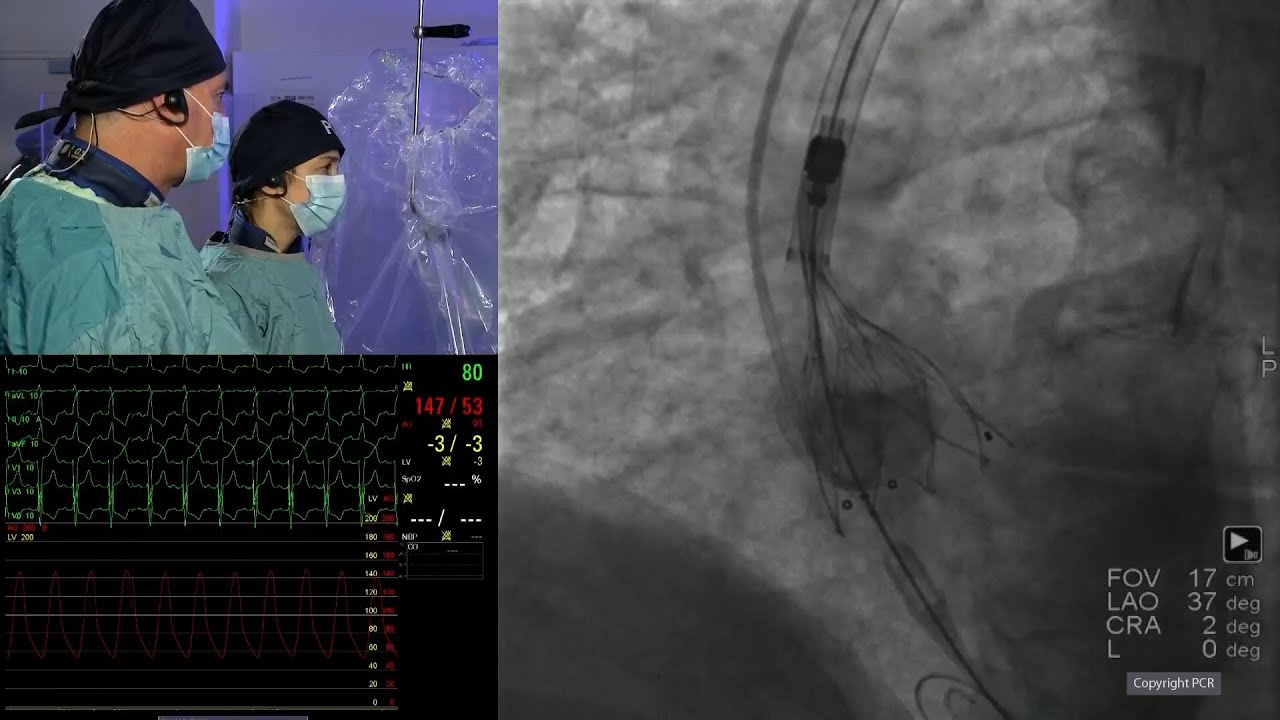

TAVI in bicuspid aortic valve disease: LIVE Educational Case from Cleveland Clinic - London, United Kingdom